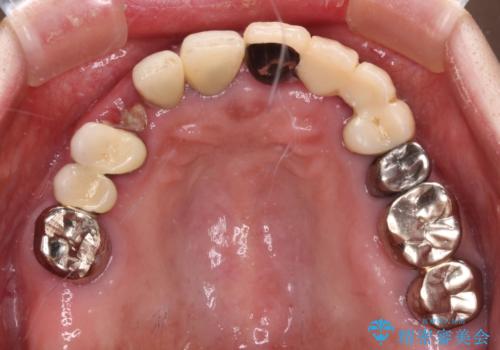

- 抜歯の必要な前歯や、以前治療した前歯のクラウンの外観を気にして来院された患者様です。

上顎犬歯や下顎大臼歯は、必要なところはインプラントを埋入することとしました。

クラウンが不適合であったり、根管治療の必要なほどの痛みのある歯であったり、見た目の気になる前歯などをオールセラミッククラウンに補綴治療を行うこととしました。